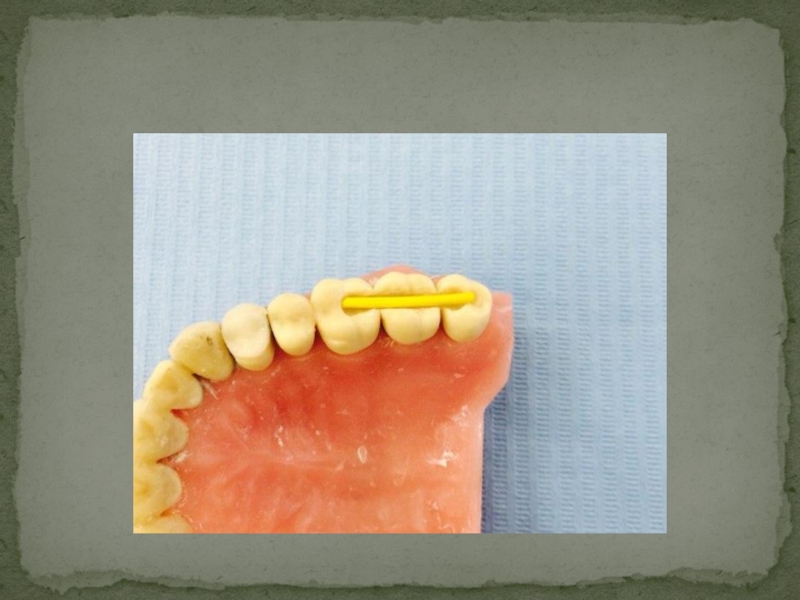

Слайд 242.Для предотвращения попадания материала в межзубные промежутки обязательно устанавливаются клинья.

2.Для предотвращения попадания материала в межзубные промежутки обязательно устанавливаются клинья.